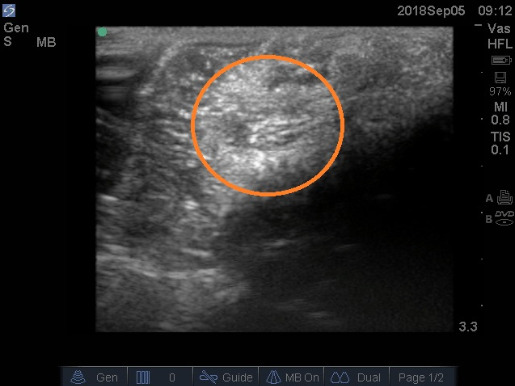

Conclusion: The authors concluded that the lipoma of this patient was not identifiable with computerized tomography imaging modalities, despite ultrasound demonstrating a hyperechoic outline of the mass in the cadaver of the patient. It is very likely that this lipoma had not been diagnosed previously due to the atypical location of the tumor. Equally, typical surgical methods associated with brachial plexopathy or NTOS treatment would be difficult or more complicated, due to the lateral and inferior location of the lipoma. Physicians treating thoracic outlet syndrome-type symptoms without resolution should consider potential non-malignant obstruction located outside the thoracic outlet, toward the extremity. Deep palpatory methods and physical therapy should be considered until diagnosis is certain, as ultrasound would be difficult and typical transaxillary surgical methods would be nonhelpful. Medical students and early-career residents and physicians should be aware of the resources provided to them via campus human anatomy laboratories which they may utilize to further their understanding and knowledge of specific pathologies.